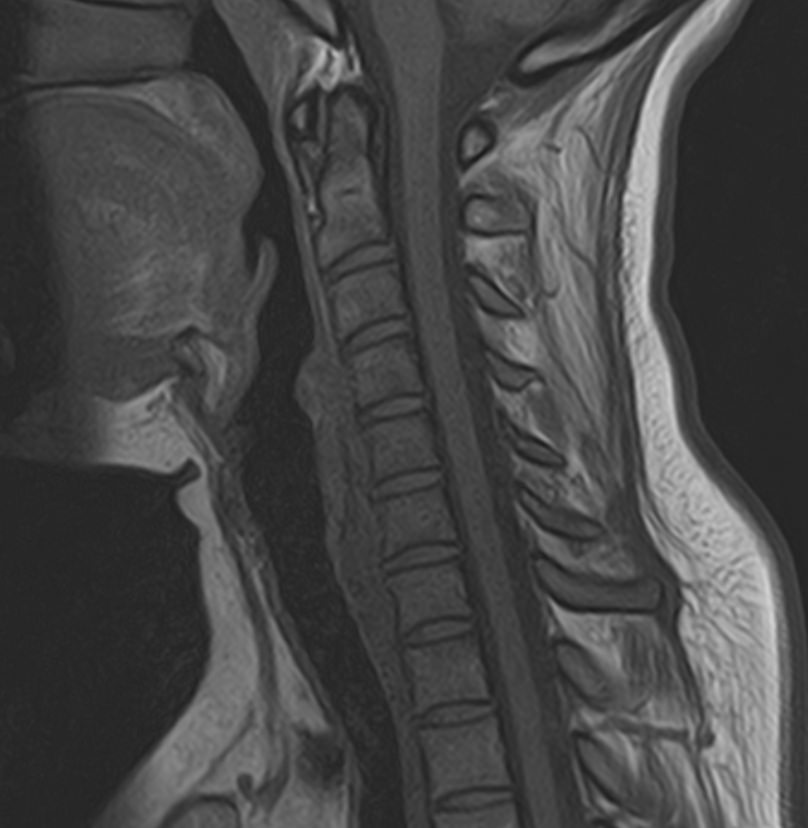

В клинике «Доступная медицина» можно пройти комплексное обследование, включающее в себя несколько протоколов сканирования близко расположенных друг от друга анатомических областей – шейного отдела позвоночника и головного мозга. Метод комплексного обследования оценивает состояние всех структур головного мозга и шейного отдела позвоночника. При этом дополнительные протоколы обследования позволяют визуализировать крупные сосуды шеи и сосудистую сеть головного мозга.

Шейный отдел позвоночника — это самый подвижный сегмент позвоночного столба, который испытывает повышенные нагрузки, подвержен травмам и развитию различных заболеваний. В эту анатомическую область входит 7 верхних позвонков, спинной мозг с отходящими от него нервными корешками.

Кроме того, в области шеи проходят крупные кровеносные сосуды, кровоснабжающие все структуры головного мозга и мягких тканей головы. К ним относятся плечеголовной ствол, сонные и позвоночные артерии, которые далее в полости черепа соединяются между собой в Виллизиев круг. Это анатомическое образование позволяет компенсировать мозговой кровоток при патологических состояниях.

Часто различные нарушения в шейном отделе позвоночника приводят к ухудшению кровоснабжения головного мозга. Опухоли и дегенеративно-дистрофические заболевания шейного отдела позвоночника могут нарушать работу головного мозга. Атеросклеротические бляшки в сосудах шеи могут стать причиной преходящих нарушений мозгового кровообращения (транзиторных ишемических атак) и привести к развитию инсульта. Поэтому важно в комплексе детально визуализировать эти анатомические структуры вместе с оценкой состояния кровеносной системы головы и шеи.

Сканирование проводится на современном высокопольном магнитно-резонансном томографе закрытого типа TOSHIBA VANTAGE TITAN 1,5 Тесла. Магнитно-резонансный томограф производит послойное сканирование исследуемой зоны в разных плоскостях, затем при помощи компьютерных программ преобразует полученные данные в трехмерные изображения. При этом кровеносная система реконструируется как вместе с окружающими тканями, так и отдельно без них.

• остеохондроз, спондилоартроз, спондилез, межпозвонковые грыжи, унковертебральный артроз, сколиоз, усиленный или выпрямленный лордоз как нарушение статической функции позвоночника, травмы, аномалии позвоночника.